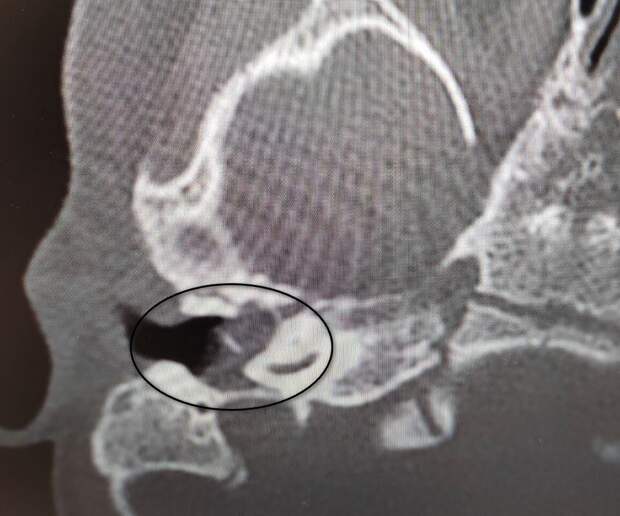

Девочка поступила в оториноларингологическое отделение больницы с хроническим гнойным средним отитом и подозрением на врожденную холестеатому барабанной полости - кистозное патологическое образование в среднем ухе.

Врачи отметили, что подобное заболевание крайне редко диагностируется у детей в столь раннем возрасте."Холестеатома опасна тем, что может привести к рецидивирующему гноетечению и разрушению структур среднего уха, отвечающих за слух", - пояснили в пресс-службе ведомства.

После обследования и подтверждения диагноза пациентку направили на операцию, в ходе которой хирурги удалили у нее холестеатому, провели декомпрессию лицевого нерва и восстановили механизм звукопроведения.